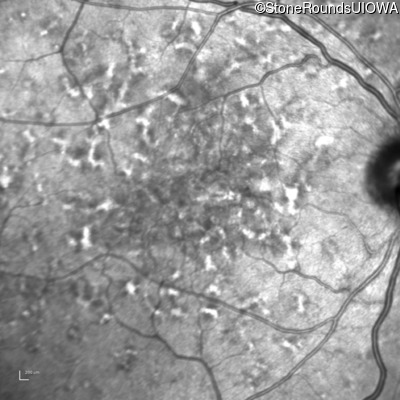

Age at visit: 49 years

This 49 year old man was first told he had a fundus abnormality on a routine eye exam at age 34. Ten years later he noticed some distortion just superior to fixation.

Pattern Dystrophy PRPH2 Gln239Stop CAG>TAG   AD